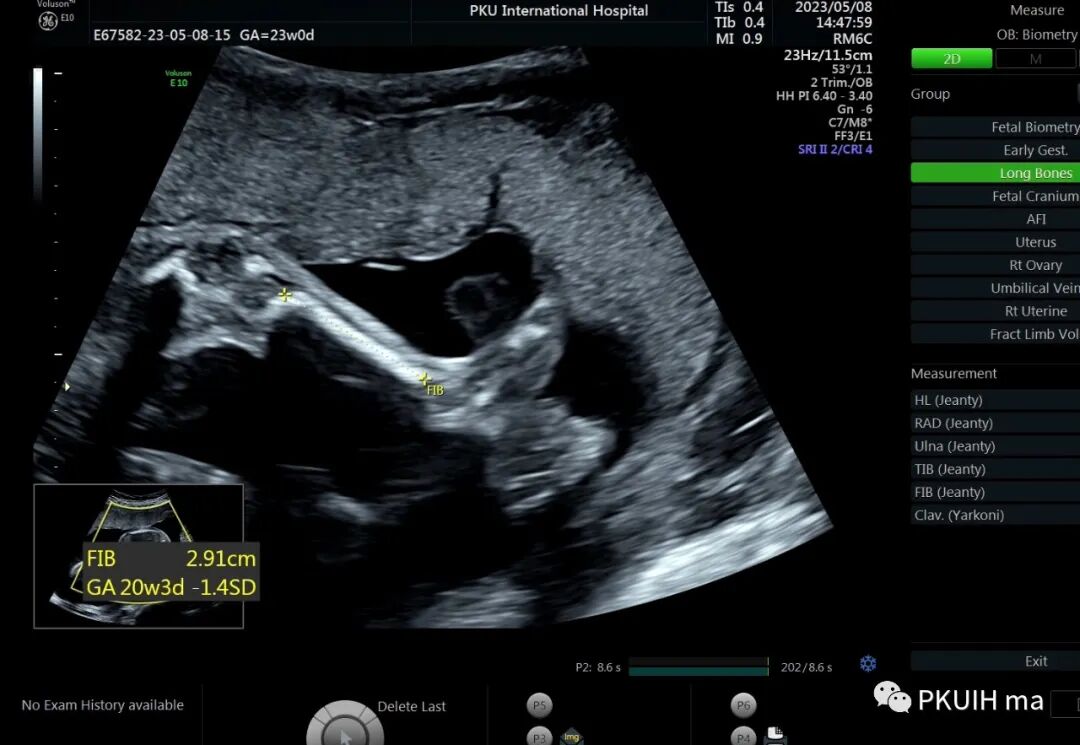

孕23周常规筛畸发现四肢长骨偏短,孕妇月经正常,核对早孕超声,孕周也没问题。

双顶径及头围正常,骨骼回声强度没有发现异常。